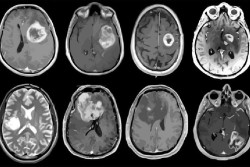

Una nueva investigación identifica las dianas genéticas de las hormonas del estrés en el cerebro

El estrés crónico es una causa bien conocida de los trastornos mentales. Ahora, una nueva investigación ha dado un paso adelante en la comprensión de cómo actúan las hormonas glucocorticoides, conocidas como hormonas del estrés, en el cerebro y cuál es su función. Los resultados, publicados en la revista `Nature Communications`, podrían conducir a estrategias más eficaces en la prevención y el tratamiento de los trastornos mentales.